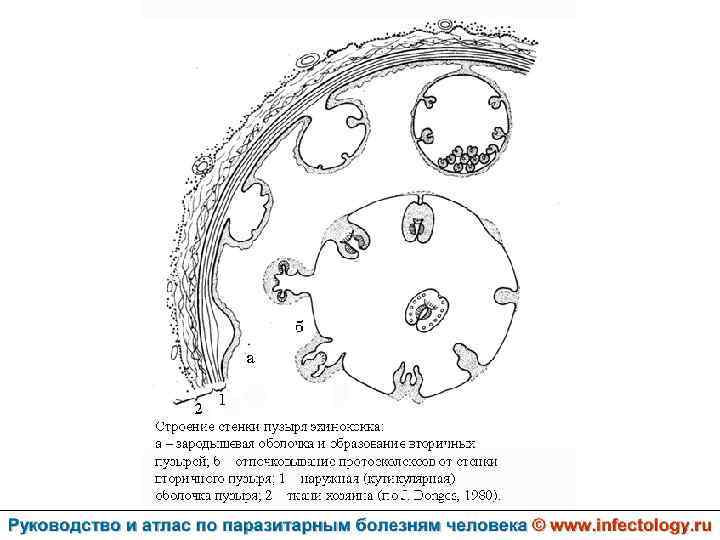

Цистный эхинококкоз (цистный гидатидоз) (шифр по МКБ 10 - B 67. 0 -4) – зоонозный биогельминтоз, характеризующийся хроническим течением, образованием кист и деструктивным поражением печени, легких и других органов.